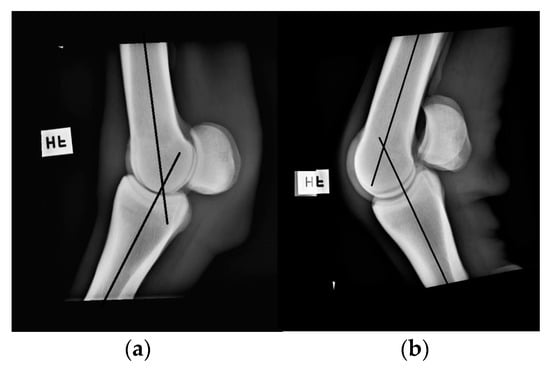

Neutral position and flexion of the right forelimb fetlock joint was measured with the DG on one healthy Standardbred trotter, separate from previous measurements. The goniometric measurements were conducted with the horse being sedated (0.3 Ml detomidin 10 mg/Ml + 0.3 Ml butorphanol 10 mg/Ml i.v.), and were done immediately before standard lateromedial radiographs (CPI Indico IQ, Ontario, Canada) were taken with the horse standing squarely (Figure 3). The measurements were then conducted on the radiographic images, serving as a “gold standard” [].

Figure 3.

Radiographic images of the fetlock joint in a (a) neutral position and in (b) flexion (photo: Nicole Gandre Lauridsen).

The results from the measurements on a sedated horse and its corresponding radiographic images showed that there was 2–3° difference depending on the joint position. Measurements of the sedated horse´s fetlock in a neutral position was 218° and on the corresponding radiographs was 216°. Measurements of the sedated horse´s fetlock in a flexed position was 138° and on the corresponding radiographs was 135°.